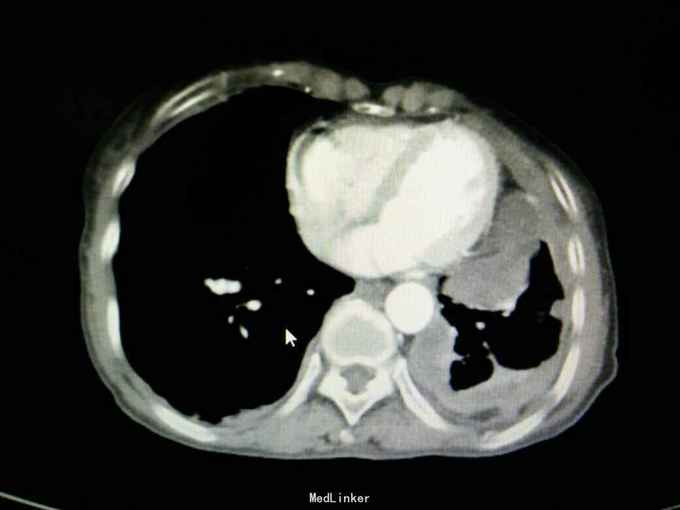

查体:神志清,精神可,生命体征平稳。两肺呼吸音粗,未闻及干湿性啰音。 辅查: 血气分析:PH7.43, 二氧化碳分压43mmHg, 氧分压77mmHg, 氧饱和度95%。 血常规:WBC7.5x10∧9/L, NE77.8%, Hb132g/L, plt231x10∧9/L。 尿常规,粪便常规,凝血功能,肿瘤标志物,CRP, 免疫功能,肝肾功能电解质无明显异常。 痰培养,痰找抗酸杆菌阴性。 心电图无明显异常。 心脏彩超:主动脉瓣局部退行性变,左室舒张功能减退,轻度肺高压。 腹部B超无异常。 胸部增强CT:双侧多发胸膜斑,左侧胸膜弥漫结节状及团块形成,考虑石棉肺伴左侧胸膜继发性恶性间皮瘤可能。

入院诊断:左侧胸膜肿物:胸膜间皮瘤? 诊治经过:予对症支持治疗,行CT引导下胸膜活检 病理:结合免疫组化和临床病史,符合恶性间皮瘤。 治疗:患者明确诊断后予化疗前预处理,择期行培美曲塞+铂类化疗